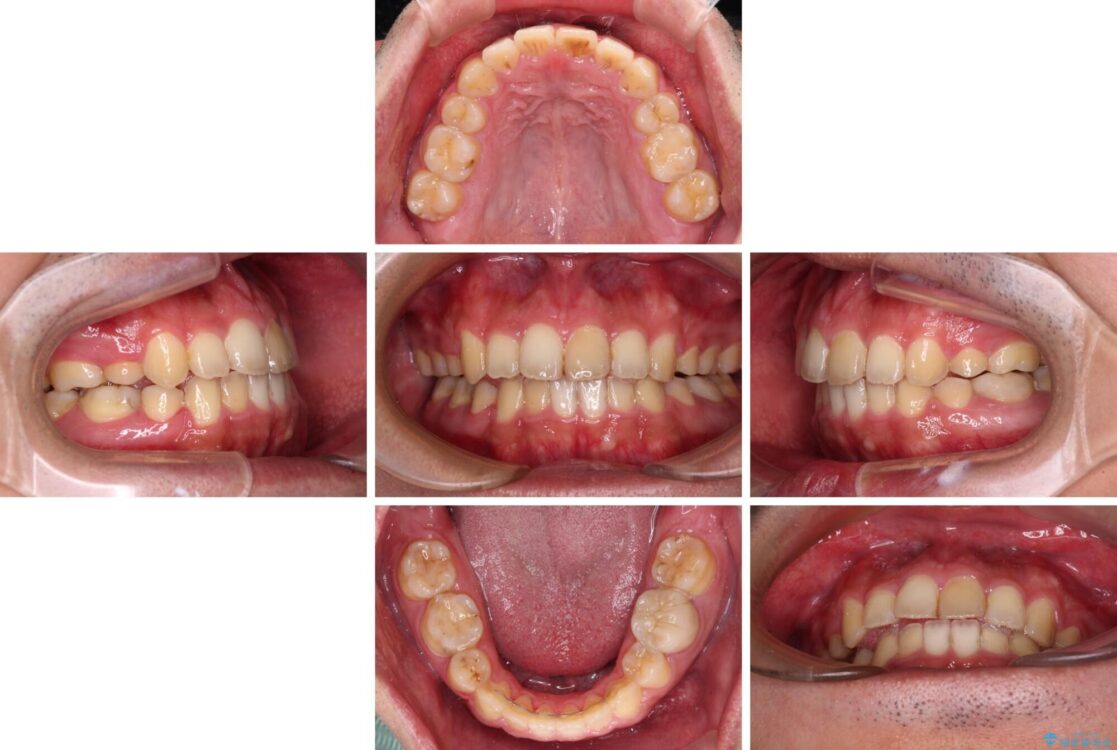

治療前

• 後戻りでデコボコの前歯 インビザライン矯正治療 治療前画像